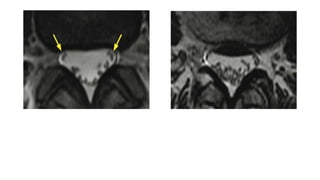

Spinal Canal Stenosis With Redundant

Nerve Roots at L3 to L4 as a result of

anterolisthesis due to facet joint

(concentric spinal canal stenosis with

hypertrophy of the ligamenta flava and disc

bulging, redundant nerve roots of the cauda

equina